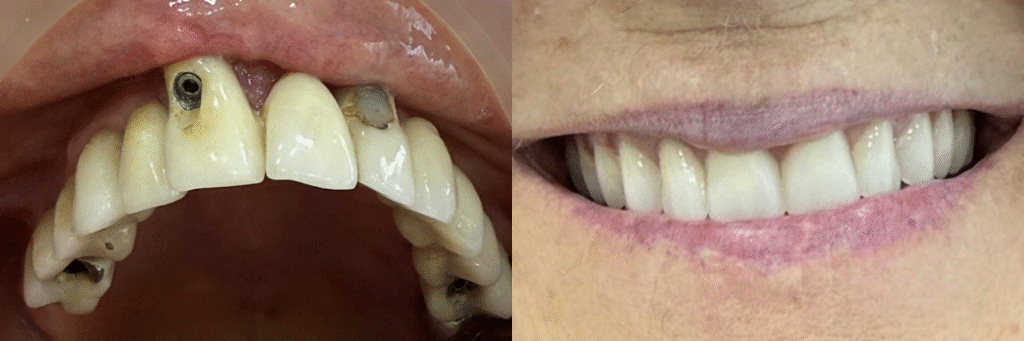

Renovación de prótesis sobre implantes